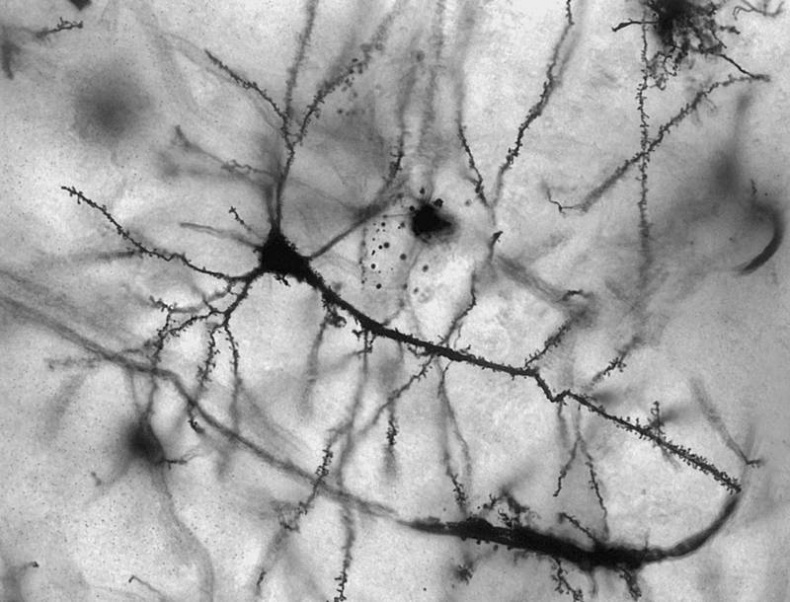

Но вот нервные клетки, как считалось до последнего времени, восстановлению не подлежат, хотя на протяжение жизни их количество в человеческом мозге неизменно убывает. А ведь это, по сути, – самый важный орган тела.

Разрушить эту устоявшуюся истину более ста лет назад, в 1906 году, попытался известный испанский гистолог и нобелевский лауреат Сантьяго Рамон-и-Кахаль. Однако «новорожденных» нейронов в головном мозге человека он не нашел.

Нейроны, которые все-таки восстанавливаются

Затем, с разницей в несколько лет, в 1962 году американский ученый Жозеф Олтман провел эксперимент, который доказывал наличие у млекопитающих нейрогенеза – возникновения новых нервных клеток в головном мозге взрослых животных. Для этого ученый с помощью электрического тока разрушил один из участков мозга крысы и ввел в него радиоактивное вещество, обладающее способностью проникать в молодые клетки. А спустя несколько месяцев Олтман обнаружил новые радиоактивные нейроны в таламусе и коре головного мозга.

И, действительно, спустя всего несколько часов после введения препарата в мозге животных обнаружились новые нейроны. Было также установлено и место, где они рождались. Им оказался гиппокамп – отдел мозга, играющий ведущую роль в формировании памяти.

Получив разрешение на исследование головного мозга пациентов, умерших от рака, ученый в конце 1998 года обнародовал сенсационный результат: в гиппокампе больных людей каждый день вплоть до их смерти возникало от пятисот до тысячи нейронов.

Ведь зная, почему в гиппокампе появляются новые нервные клетки, ученые смогут заставить обновляться и другие части мозга. А это, в свою очередь, поможет справиться с некоторыми болезнями мозга и последствиями его травм.